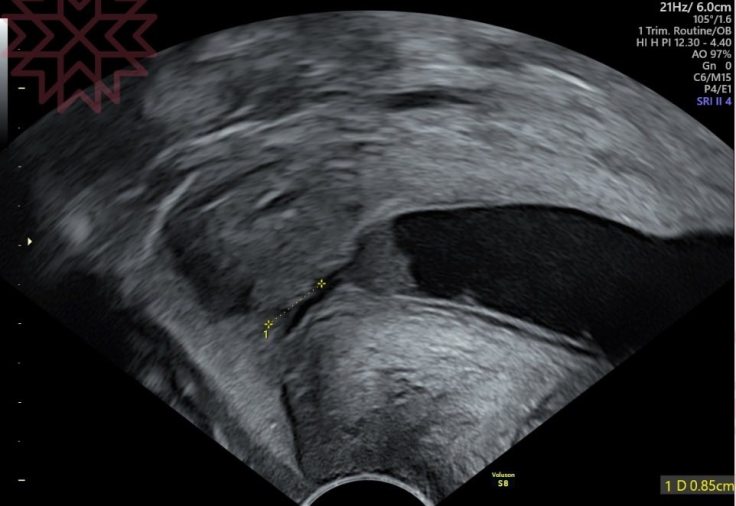

超音波探頭放下去一看

我看到心臟都快跳出來了

不是比較短

是只剩0.85cm

(正常防衛線容許最低標準是2.5cm

是城牆快要整個被攻破了。